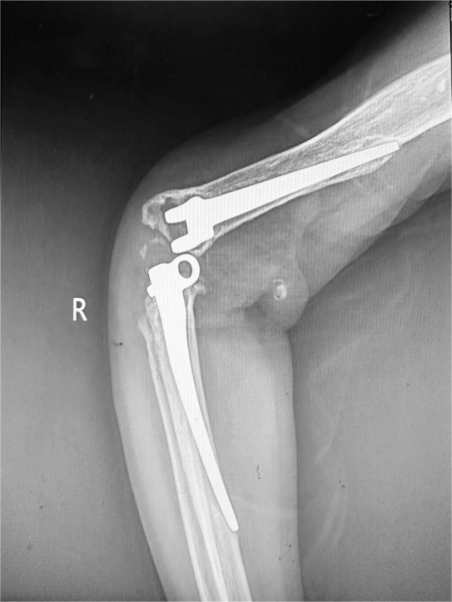

患者是一名55岁的中年男性,23年前因严重车祸伤于我院由王坤正教授完成右肘关节置换术,术后恢复良好。1年前患者再次出现右侧肘关节疼痛,外院肘关节X片提示假体转轴磨损脱落合并脱位。患者第一时间联系了我科,要求行翻修手术。入院时右侧肘关节无活动度,功能基本丧失,患者的工作和生活受到了极大的影响,深感痛苦。

与其他人工关节置换术相比,全肘关节置换术在设计和手术技术上要求更高。肘关节的复杂运动特性使得术后假体活动和稳定性的控制成为一大挑战。此外,假体在各种体位和活动中的松动、断裂和磨损风险,对手术医师的操作准确性与熟练度提出了严格要求。该患者术前肘关节假体肱骨侧及尺骨侧均几乎穿出骨皮质,髓腔形态异常,为确保手术成功,关节与足踝病区团队完善术前讨论,为该患者设计了个性化的3D打印肘关节假体,并提前模拟了手术假体安装过程。在王坤正教授的指导下,杨佩教授、王春生副主任医师经过精细操作,最终使这一例复杂肘关节置换术最终成功实施,使患者可以更快地恢复肘关节功能,进行正常的日常生活活动,提高生活质量。